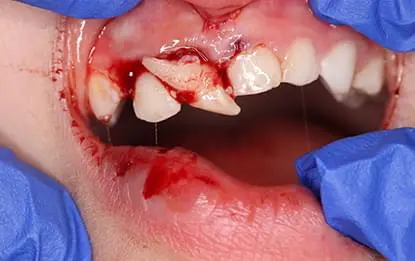

Травма зуба - те, що може статися з будь ким і в будь який момент. А особливо це стосується дітей, які починають активно освоювати навколишнє середовище. Тому знати і вміти зреагувати на травму тимчасового зуба є стратегічно важливим для дитячого стоматолога. Наш курс буде корисний усім стоматологам, адже звернутись з травмою можуть до кожного стоматолога.

Травма постійного зуба у дитини - одна з найскладніших задач для дитячого стоматолога. Знати, розуміти, вміти надати допомогу - стратегічно важливо, оскільки може стояти питання збереження зуба на майбутнє у дитини. Наш курс саме для того, аби озброїти лікарів відповідним знаннями і вміннями. Курс стратегічно важливий для кожного лікаря-стоматолога: дитячого, загального чи будь-якої іншої спеціалізації. Особливо рекомендований для лікарів-інтернів та студентів, оскільки на реальних клінічних випадках дозволить побачити різні рішення лікування травми постійних зубів у дітей і в потрібний момент допомогти дитині зберегти постійні зуби.